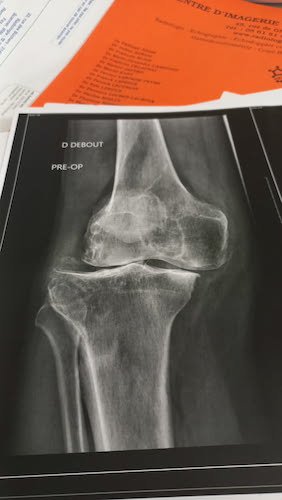

Figurez-vous qu’après Daniel ( viewtopic.php?t=2333 ), j’ai rencontré Miguel qui m’a donné 2 photos de son genou opéré. Une prise AVANT l’opération et l’autre APRÈS.

La photo du genou de Miguel AVANT.jpg

La photo du genou de Miguel AVANT.jpg (19.88 Kio) Vu 4025 fois

La photo du genou de Miguel APRÈS.jpg

La photo du genou de Miguel APRÈS.jpg (30.23 Kio) Vu 4025 fois

Miguel a une pêche d’enfer. Il devrait reprendre doucement le vélo en juin et a prévu de nous montrer son dossard en septembre quand il reviendra dans le peloton de la Carrerrasse.